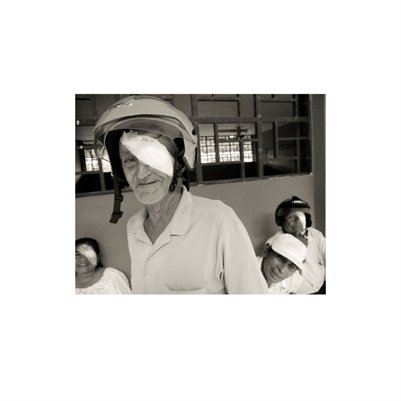

Darkness into the Light. In 2012, The Amazon Project gave eye care to nearly 6000 patients within a 200 kilometer radius of their base in Leticia, Colombia.